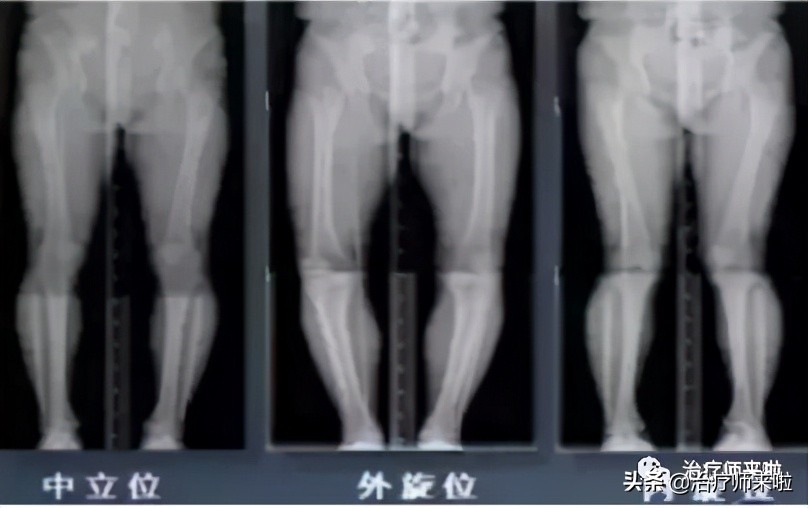

1、影像学检查: X线检查,如上图所示